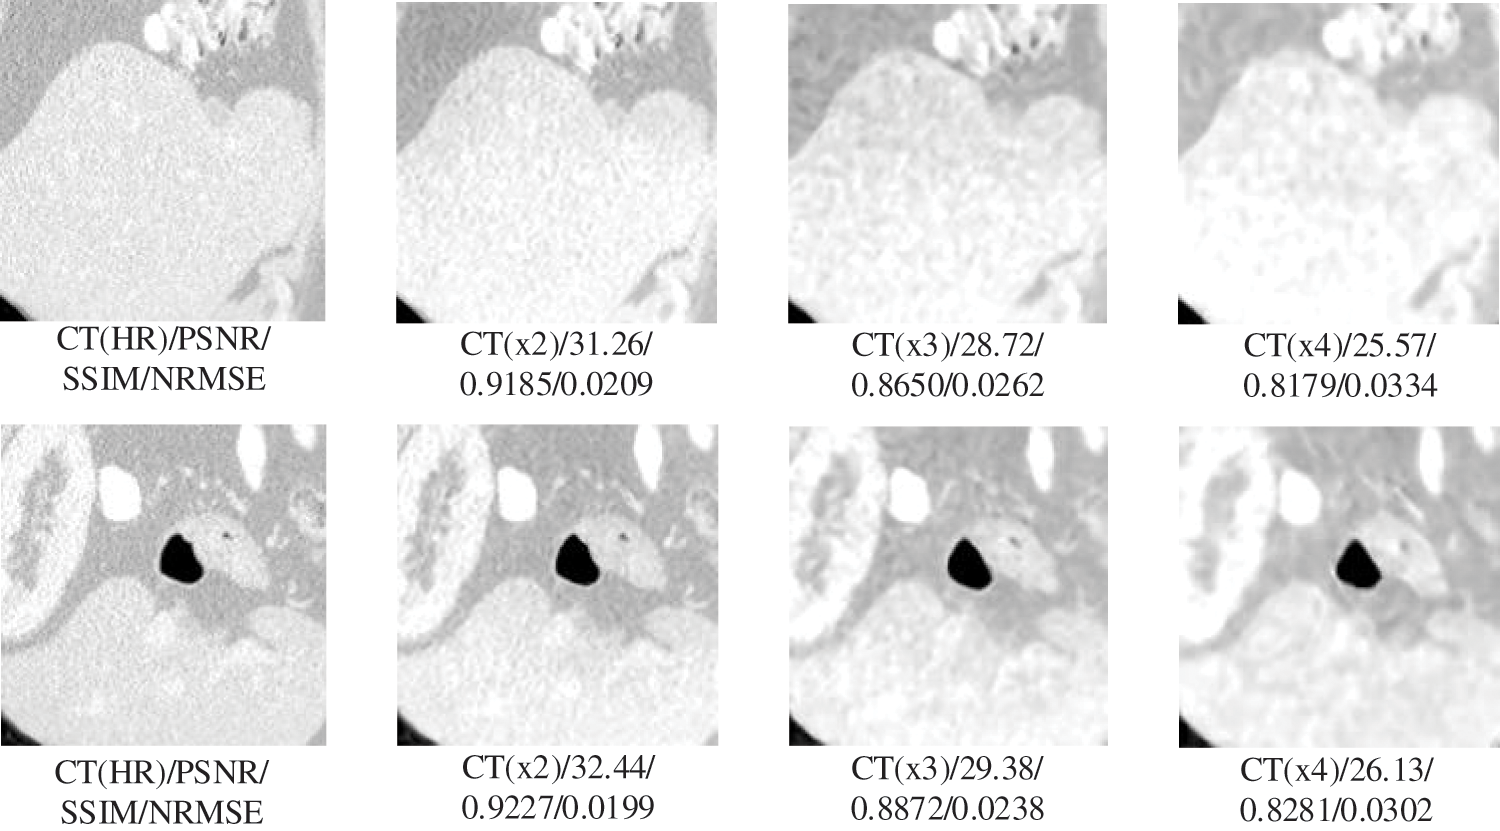

In this section, we will test the generalizability of the network using CT slices from three locations: pelvis, chest, and liver. Testing whether the network can have large enough adaptability that a single set of training for but one site can meet the SR requirements for multiple sites, allowing the network to have higher convenience without needing repeated training operations for different site intervals. The experimental results are shown in Figs. 4 and 5. The specific experimental data are shown in Table 3.

Figure 5: Generalization results of multiscale SR on liver images

The results in Table 3 show that our proposed SR algorithm is superior in terms of generalization to different parts compared to the two deep learning SR methods. The test sample used in the lung visualization results in Fig. 4 is a 512 × 512 slice, while the liver test sample in Fig. 5 is a 160 × 192 slice. Comparing the SR results of the two figures shows that the SR processing results are better at high magnification when the LR image contains more information. Although the 4x SR results are not ideal in the liver, the quality of the results of 2x SR is sufficient for use. Therefore, it can be verified that the generalizability of our proposed method to different sites is also excellent.